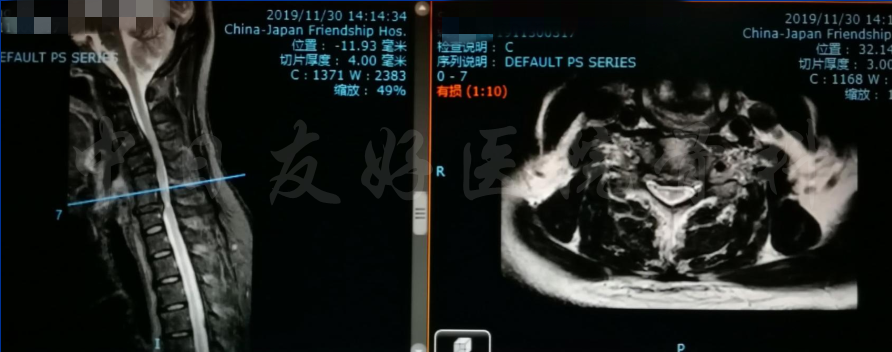

腰椎MRI

轴位MRI:腰3-4(左)、腰4-5(中)、腰5骶1(右)

2019年11月30日 颈椎MRI提示:颈3/4颈4/5颈6/7椎间盘突出,椎管狭窄;颈5-6水平脊髓异常信号,变性可能。

颈椎MRI

颈椎MRI

颈椎各节段MRI(上下滑动)